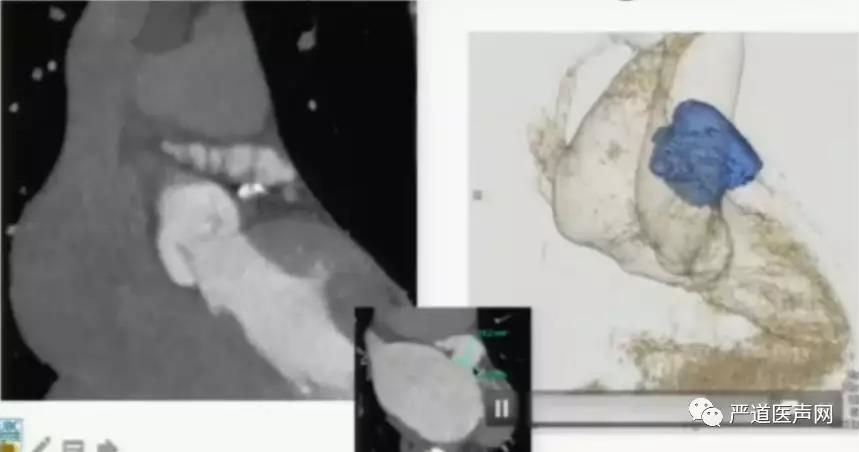

利用CTA三维重建构建出左心耳的形态(如上图),用于术前模拟手术植入的过程,以此方法可以评估左心耳的分叶情况,对固定盘及封堵盘的尺寸选择提供精确参考,还有利于指导术者进鞘的操作和途径。

术前LAA的造影结果及3D成像